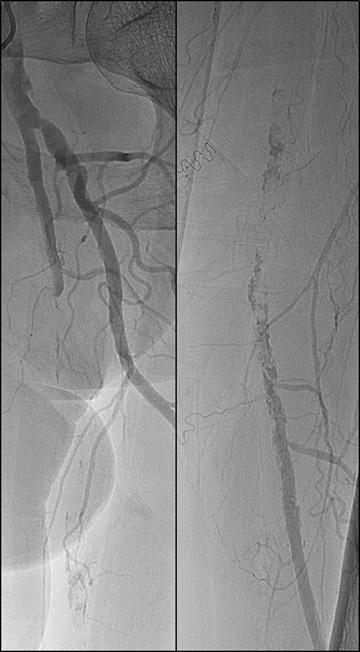

n PERIPHERAL ARTERIAL DISEASE:

Crossing chronic total occlusion lesions are challenging procedures. The BeBack crossing catheter—Bentley’s first product to be available in both Europe and the USA following the company’s acquisition of Upstream Peripheral Medical Technologies’ GoBack crossing catheter in September 2022— offers a new solution in this space. In a Bentleysponsored advertorial, Andrej Schmidt (Leipzig, Germany) shares his clinical experience with the BeBack, noting how it has been a “gamechanger” in his endovascular peripheral arterial disease practice.

For more on this story go to page 19.